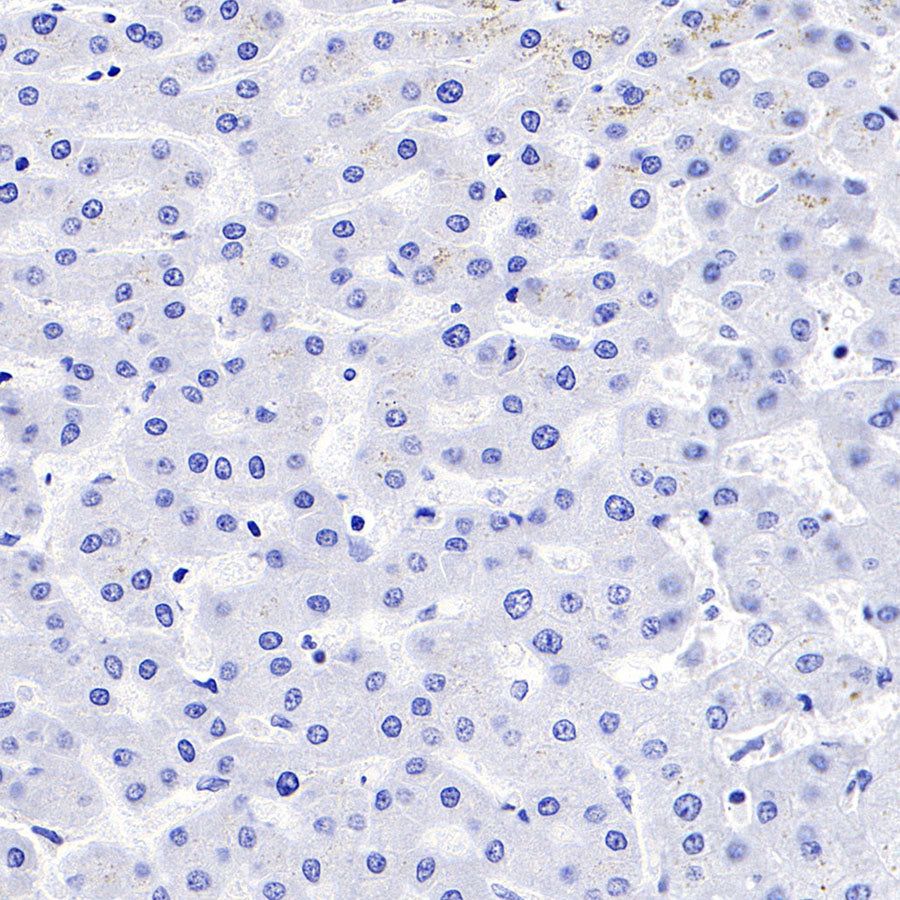

Negative control: IHC shows negative staining in paraffin-embedded human liver. Anti-PD-1 antibody was used at 1/500 dilution, followed by a HRP Polymer for Mouse & Rabbit IgG (ready to use). Counterstained with hematoxylin. Heat mediated antigen retrieval with Tris/EDTA buffer pH9.0 was performed before commencing with IHC staining protocol.